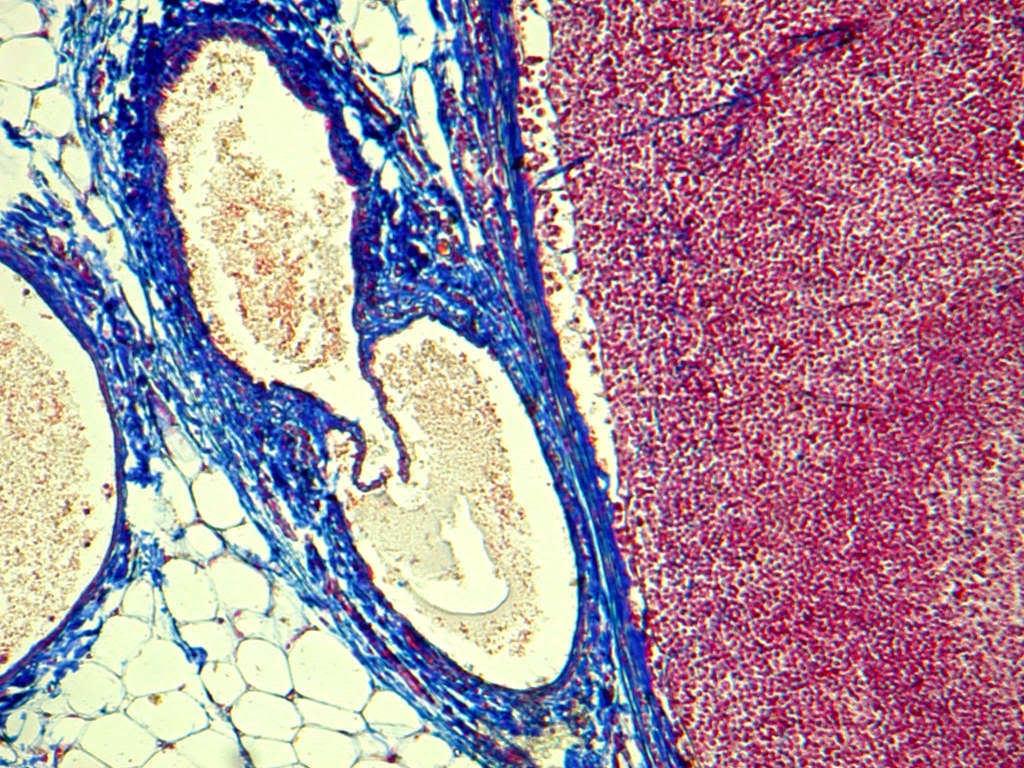

Grau ist alle Theorie, jedoch mit farbig bunter AZAN-Färbung sehen die rein mechanisch arbeitenden Pumpventile des Lymphsystems am schönsten aus. So schön, dass man auch deren Funktion leicht erkennt:

Zum Lymphknoten (hier eines Hundes, rechts im Bild) hin führen die Sammelgefäße der regionalen Lymphdrainage. Die Lymphe fließt über den Knoten zum Herzen hin, steht aber nicht mehr unter (arteriellem) Druck und muss daher passiv durch die Lymphgefäße gepumpt wrden. Dazu diesen die schleußenartigen Ventile mit zwei Klappen, die einen Durchfluß nur in eine Richtung erlauben.

Im Querschnitt (ein etwas unscharfes Photo eines Studentens) erkennt man die Konstruktion: Die beiden Lappen der Lymphpumpe hängen wie ein Schlauch zwischen den Bändern. Mit der Muskelbewegung wird die Lymphe durch dieses Ventil zum Lymphknoten hin gepresst.